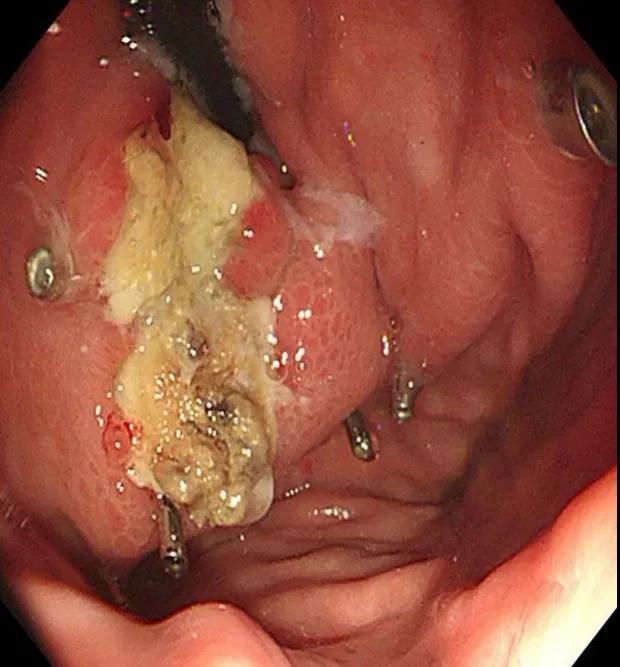

術中治療:胃底鈦夾夾閉部分靜脈,分三處共注射組織膠3.5ml、聚桂醇6ml。

術后復查胃鏡及血管成像

一月后復查胃鏡及門脈血管成像檢查可以看到患者分流道消失,胃底巨大靜脈團消失,出現(xiàn)輕度的排膠反應,患者恢復良好。